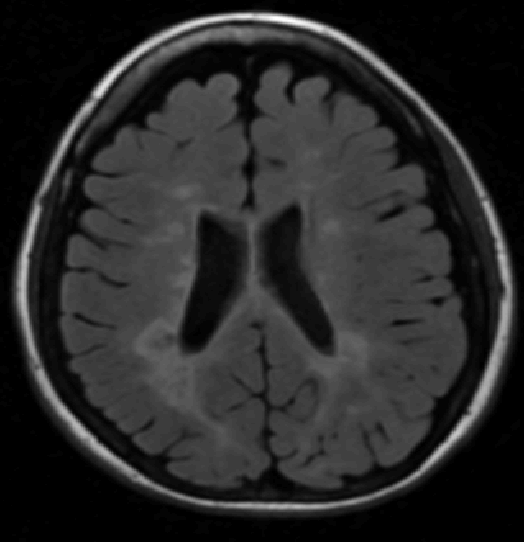

We use images from three different studies (see Fig. 1 for examples of slices):

10 MS patients from the MS Lesion Challenge [11] scanned at the Children’s Hospital of Boston (CHB), scanned with T1, T2 and FLAIR at 0.50.50.5mm resolution.

10 MS patients from the MS Lesion Challenge [11] scanned at the University of North Carolina (UNC), scanned with T1, T2 and FLAIR at 0.50.50.5mm resolution.

- 3.

Here again the differences between study populations influence the class priors. On average, the percentage of voxels that are lesions are 1.6%, 2.6% and 0.2% in CHB, RSS and UNC respectively. The differences between subjects also vary: these are relatively small for CHB and UNC, but very large for RSS. In RSS, the subject with the least lesion voxels has only 0.08%, while the patient with the most lesion voxels has 14.3%.